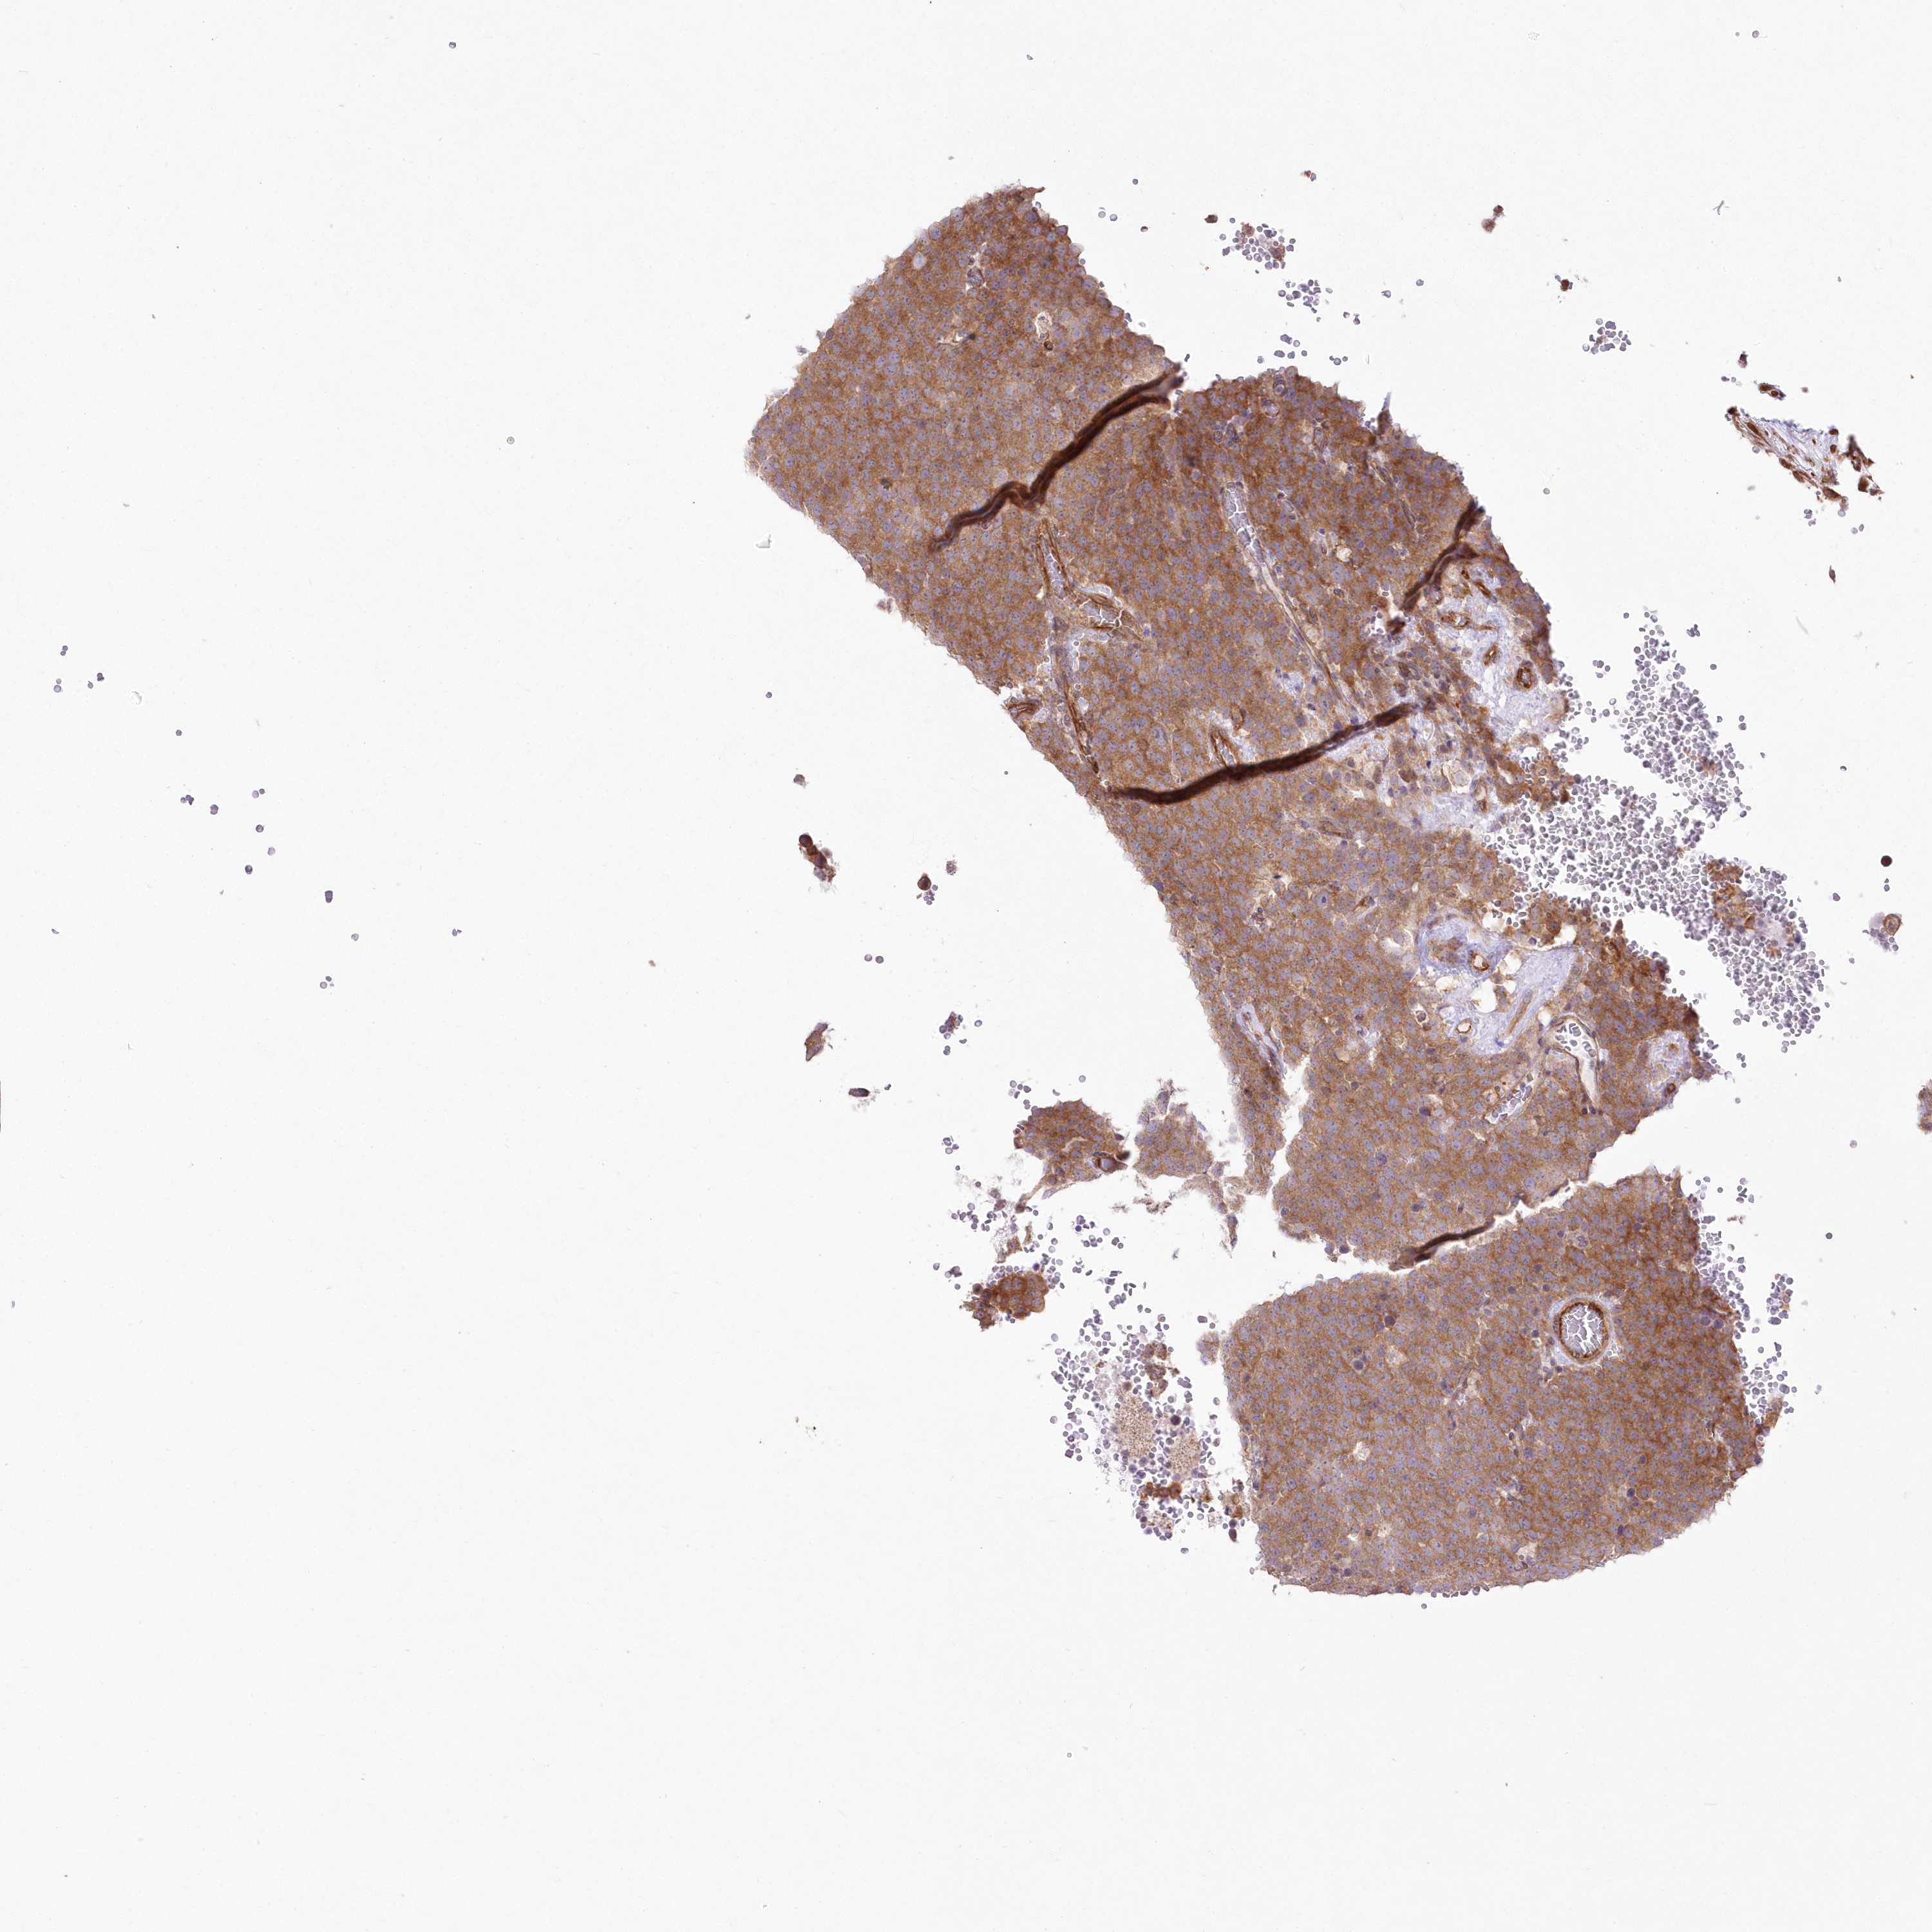

TESTIS CANCER - Protein expressioni

A mouse-over function shows sample information and annotation data. Click on an image to view it in a full screen mode. Samples can be filtered based on level of antibody staining by selecting one or several of the following categories: high, medium, low and not detected. The assay and annotation is described here.

Note that samples used for immunohistochemistry by the Human Protein Atlas do not correspond to samples in the TCGA dataset.

Antibody stainingi

Antibody staining in the annotated cell types in the current human tissue is reported as not detected, low, medium, or high, based on conventional immunohistochemistry profiling in selected tissues. This score is based on the combination of the staining intensity and fraction of stained cells.

Each image is clickable and will lead to virtual microscopy that enables deeper exploration of all samples and also displays staining intensity scores, fraction scores and subcellular localization as well as patient and tissue information for each sample.

Antibody HPA036471

Staining

High

Medium

Low

Not detected

Intensity

Strong

Moderate

Weak

Negative

Quantity

>75%

75%-25%

<25%

None

Location

Nuclear

Cytoplasmic/membranous

Cytoplasmic/membranous,nuclear

Carcinoma, Embryonal, NOS

Seminoma, NOS

Urothelial carcinoma, High grade